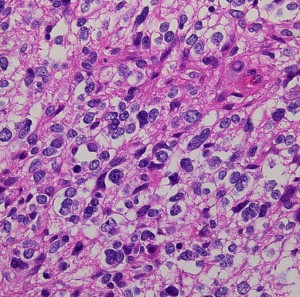

下の病理写真は,ある患者さんから私に送られたものです。20代で前頭葉の膠芽腫になってから21年経って生存しておられるということです。2度の開頭術と放射線治療と化学療法(複数回)を受けておられます。患者さんに病理診断が間違っているのではないかと返事をしたら,下にある画像を送ってくださいました。病理診断は,一見したところは多形膠芽腫 グリブラに間違いありませんでした。でも,ーーー

(下の画像は患者さんの許可を得て掲載させていただきました)

bizarre! 異様な細胞が混在しています。核多型が目立ち,多核巨細胞も混じる典型的な膠芽腫の像です。下の左の画像は血管内皮の肥厚 endovascular proliferationがあり,下の右のKi-67染色では核濃染像が多く核分裂能が高いことを示します。しかし,——

左のGFAP染色では一部の細胞が染色されません,右のHE染色では豊富な血管増殖の間に空砲 perinuclear halo を有した細胞増殖が見られます。さらに,–

腫瘍の部分像として明らかに乏突起膠腫が混在しています。また,どの部分をみても壊死 necrosisがありませんでした。

従って,当時の診断では,この腫瘍の形態病理診断は,退形成性乏突起星細胞腫 anaplastic oligoastrocytoma WHO grade III となります。2018年時点では,もしiDH変異があったと仮定すると,secondary glioblastoma (IDH-mutated glioblastoma)とされるかもしれません。